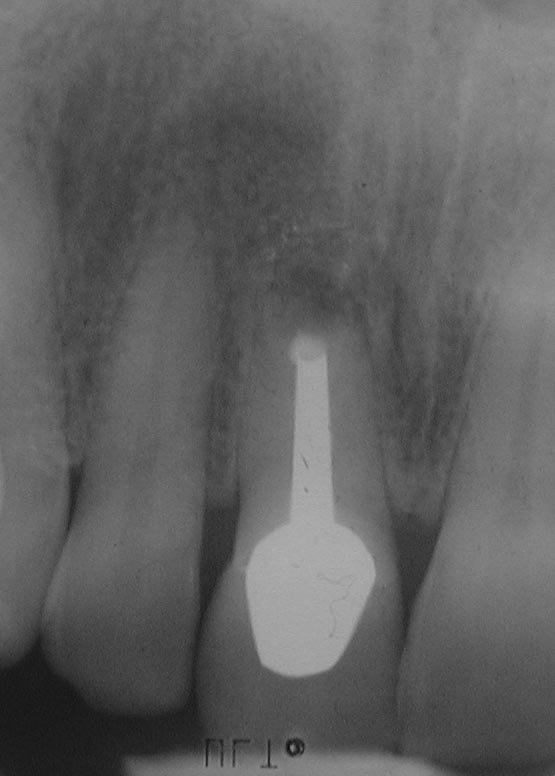

BB-1

555 × 776

(Miss)Erfolg des Tages